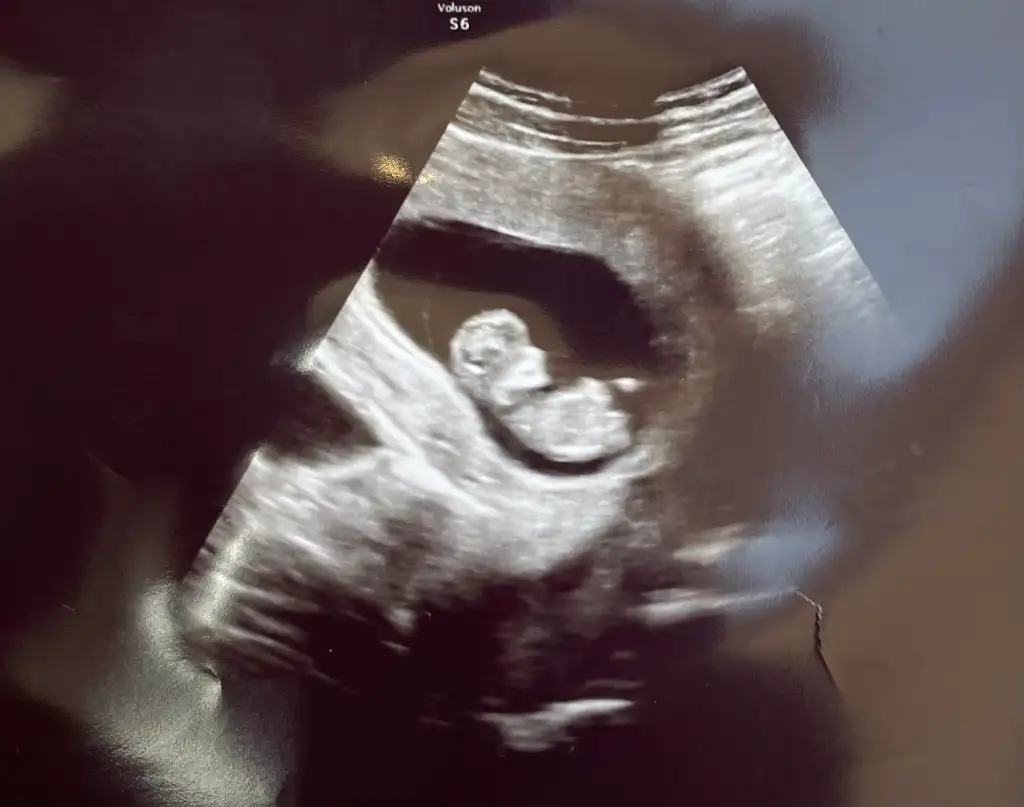

Başka fotoğraf var mı? Kafa şekli biraz yuvarlak gibi. Kıza benziyor bu haliyle ama ultrason tuşuna göre bile degisebiliyorNormalde 10+2 günlük ama ultrasonda 10+5 günlük çıktı. Cinsiyet tahmini yapabilecek var mı? Şuan erken biliyoruminsan merak ediyor

Ay maşallah ne güzel poz vermişNormalde 10+2 günlük ama ultrasonda 10+5 günlük çıktı. Cinsiyet tahmini yapabilecek var mı? Şuan erken biliyoruminsan merak ediyor

Başka yokBaşka fotoğraf var mı? Kafa şekli biraz yuvarlak gibi. Kıza benziyor bu haliyle ama ultrason tuşuna göre bile degisebiliyor

Hangi teorileri uyguladınBaşka yok. Bütün teoriler kız diyor. Ama erken tabi. Hayırlısıyla 2 hafta sonra ikili test var. Orada detaylı bakılacak. O zaman belli olur diye düşünüyorum. Gönlümden kız geçiyor ama sağlıklı olsun da önemli olan o

nub ve ramzi teorilerine göre erkekmişNormalde 10+2 günlük ama ultrasonda 10+5 günlük çıktı. Cinsiyet tahmini yapabilecek var mı? Şuan erken biliyoruminsan merak ediyor